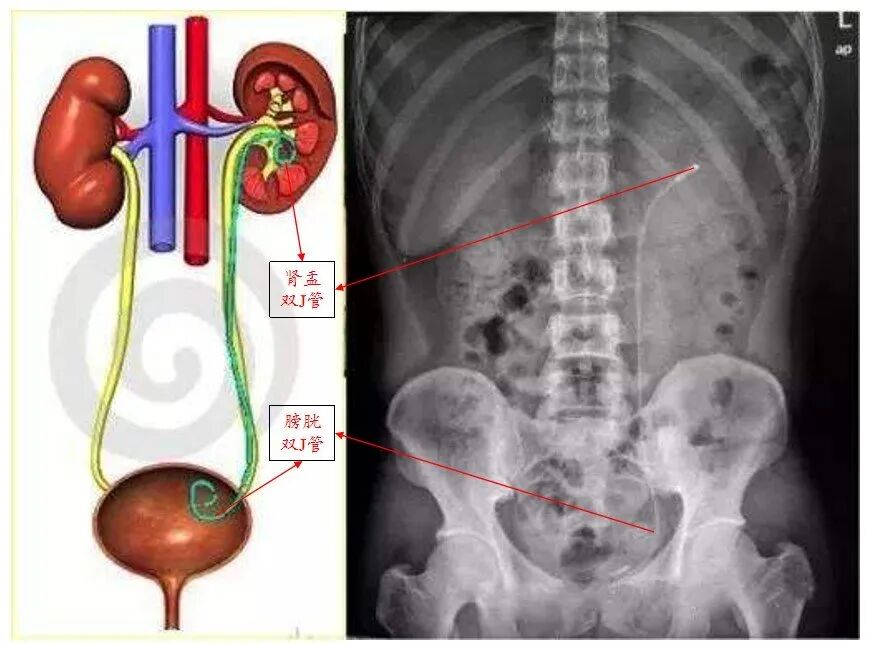

泌尿系结石碎石术后需常规放置输尿管支架,因其两端卷曲形似英语字“J”而取名“双J管”,又因为形似猪尾巴,又被叫做“猪尾巴管”。输尿管支架在体内一端位于肾脏内,一端位于膀胱,由于其对输尿管有着支撑和内引流的作用,能解除输尿管炎性水肿造成的暂时性梗阻,防止术后伤口漏尿、输尿管狭窄以及结石碎片堵塞。